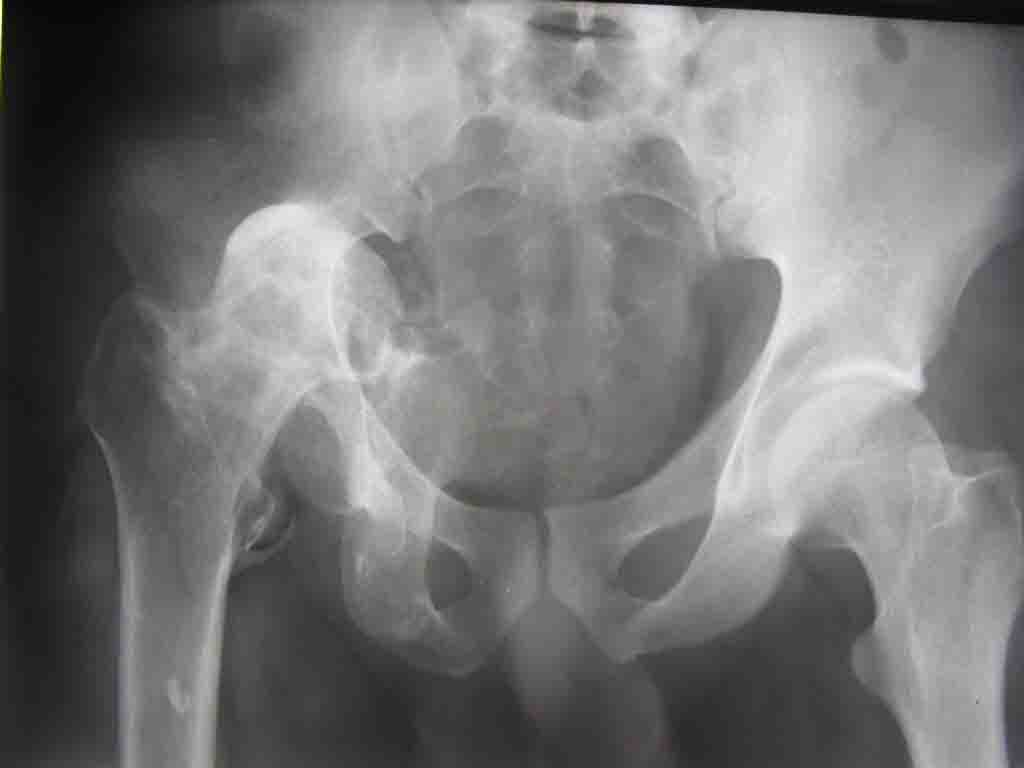

Уважаемые коллеги! На консультацию пришел молодой человек 23 лет с застарелым задним вывихом бедра. После травмы прошло 2,5 ГОДА.

Были переломы бедра и голени на этой же стороне, которые благополучно срослись после остеосинтеза. вывих бедра был пропущен. В настоящее время ходит без дополнительной опоры, есстественно, сильно хромает, выражен болевой синдром, парез седалищного нерва. Сформировался неоартроз в подвздошной области, виден неправильно сросшийся перелом задней колонны, сгибание в суставе до 80.

Что делать? Честно говоря, на таких сроках опыта лечения подобных больных нет (мах 8 мес). Постепенно низводить аппаратом и затем ставить эндопротез там где должен быть сустав? Или ставить протез выше истинной впадины с укорочением конечности, а затем удлиннять бедро или голень? У кого есть подобный опыт, подскажите?